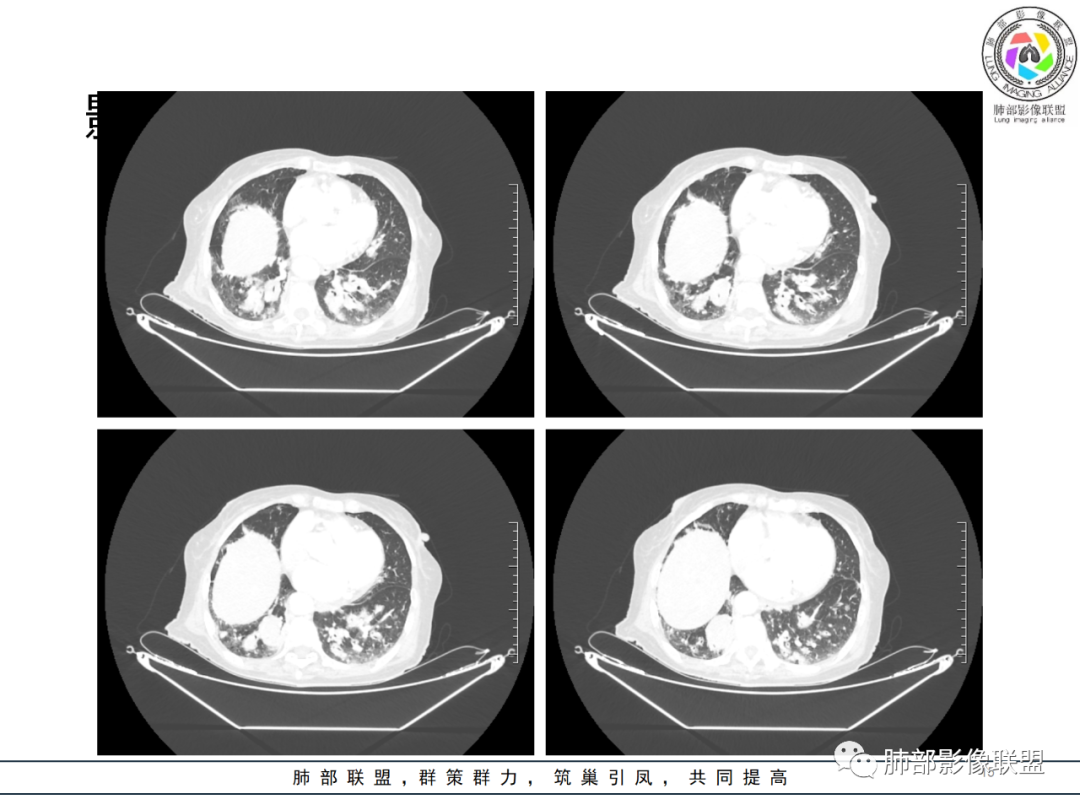

影像资料

82岁女性,反复发热入院,查外周血白细胞升高,抗生素治疗可缓解,支持细菌感染性发热,结合肾脏肿瘤,考虑泌尿系感染发热;CT提示双肺多发毛玻璃影,右下肺多发大结节影,3月复查,双上肺毛玻璃影/混合毛玻璃影增多,部分呈点晕征,右下肺多发肿块,可见支气管穿行,双下肺中轴间质增厚,左肾占位,肺部病变考虑:1.淋巴瘤 2.肾癌肺转移

右肺下叶近胸膜面多个实性结节,复查体积明显增大,多个新增实性及混合磨玻璃结节,边缘晕征,左肾及肾上腺占位,考虑囊性肾癌肺内、肾上腺转移。

右肾肾上腺,左肾及肾周软组织,脾脏可疑病变,双肺结节斑片支气管血管束叶间裂分布。一元考虑大B淋巴瘤多器官浸润。鉴别小细胞,尿路上皮癌转移,igg4

老年女性,近期反复的发热,胸部CT基础尚可,心影增大,双肺下叶血管束增粗,3个月后复查 提示双肺多发磨玻璃密度影,并有磨玻璃影内部血管的穿行,双肺下叶血管束的增粗,纵隔窗下未见纵隔肿大的淋巴结,血管通畅,未见血管壁的增厚,左肾肿瘤?肺内病变不符合支气管束分布,暂不考虑吸入性,考虑淋巴管或血管源性病变。总体考虑非感染性病变可能性大,血管炎?淋巴瘤?

三月后患者再次因发热就医,病灶在“原址”基础之上范围扩大,病灶增多(而非此起彼伏),就有些不同寻常,仅如此高龄,如此大范围感染,持续三月之久?太难以想象。

两肺多发病灶,沿支气管血管束分布,缺乏多形性特点,始终未见空洞,没有此起彼伏,没有其他旁证,血管炎的诊断似乎缺乏支撑。

恶性肿瘤自然会纳入视野,如“肺炎型肺癌”(如粘液腺癌、腺癌),转移癌,淋巴瘤(包括淋巴瘤样肉芽肿)等等,有些病灶可以进展比较快。“肺炎型肺癌”、淋巴瘤等病灶常见支气管穿行,来自泌尿系统的透明细胞癌的转移也常常可以气道相关。